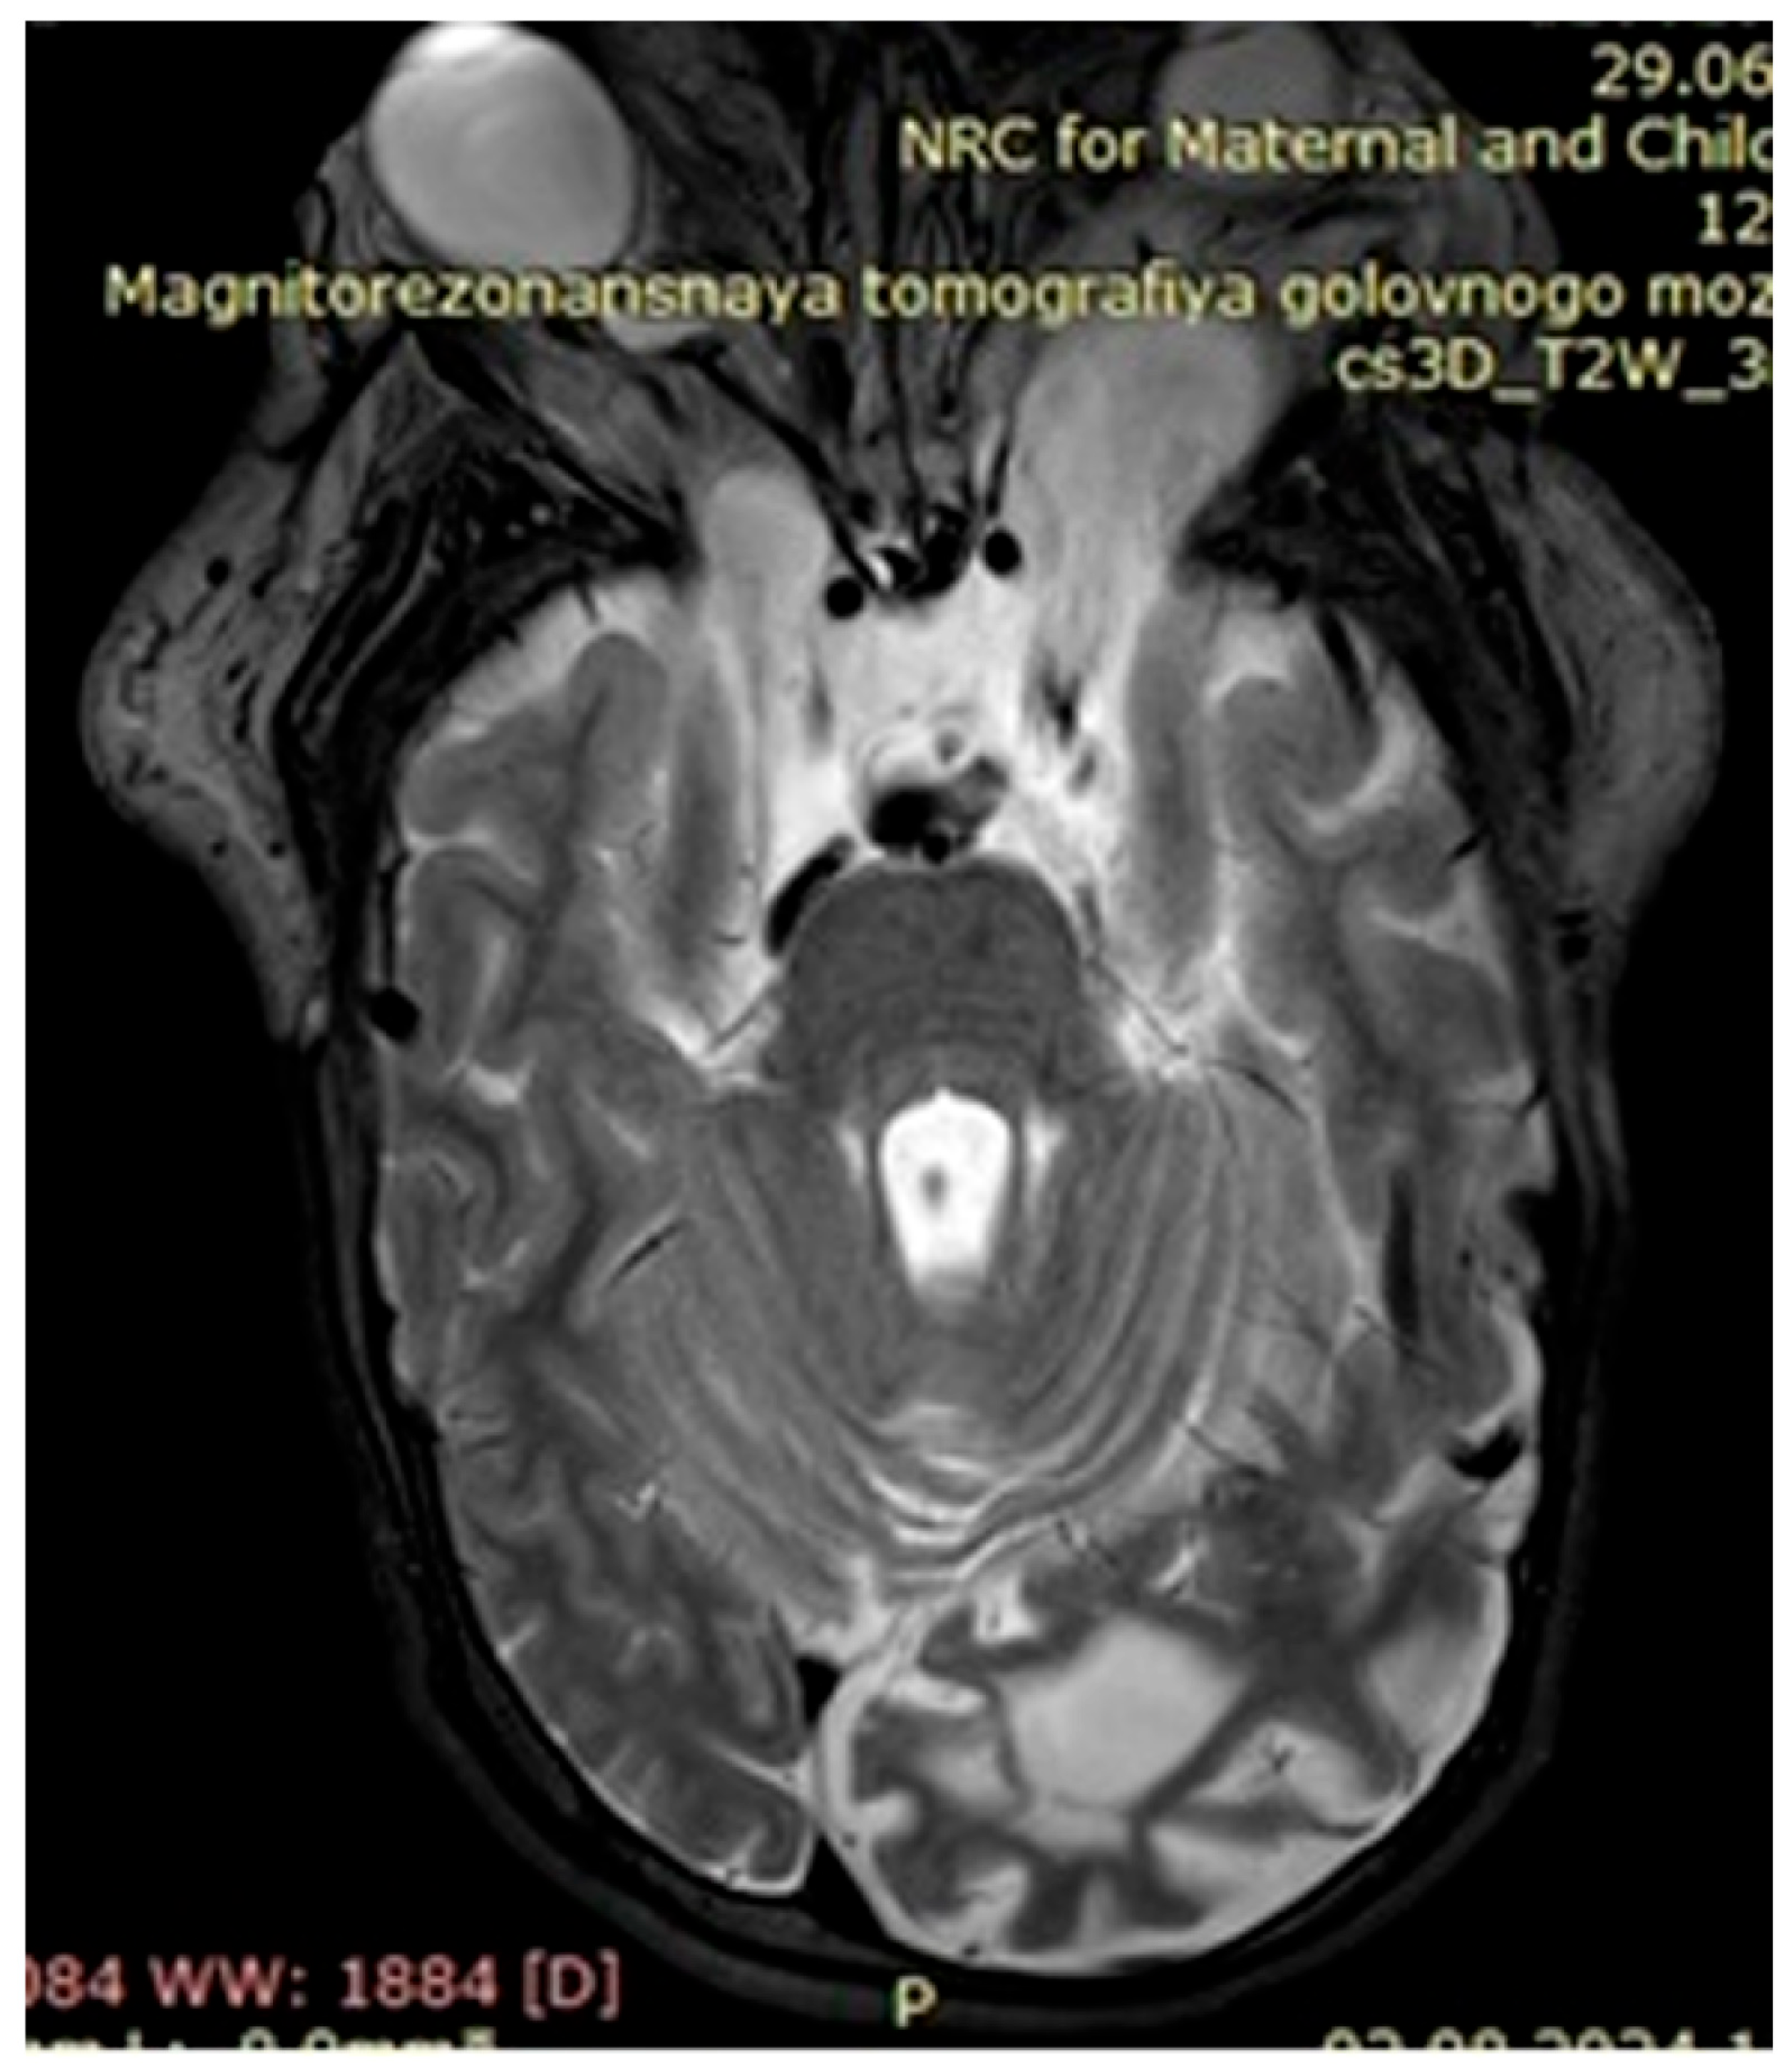

The observed café au lait macules originated in the early childhood of our patients and in most cases grew as they approached adolescence. Around 60% of patients with neurofibromatosis had two, simpler neurofibromas, characterized by nerve hypertrophy, which in turn caused displacement of adjacent tissues, organs, and bones if located next to the pelvis and/or spinal cord. There were several patients presenting with severe cases of scoliosis, lordosis, and torsion of the rib cage due to ongoing growth of neurofibromas, identified via MRI as focal areas of increased signal intensity, with space-occupying lesions verified on the T2-MRI STIR (Short Tau Inversion Recovery) regime as plexiform neurofibromas.

Upon further growth of neural tissues, patients presented with plexiform neurofibromas, located around the eye tract, neck, spinal cord, and groin (examples presented in Figure 3, Figure 4 and Figure 5). A total of 14 patients presented with optic nerve and optic tract glioma as well as retinopathies, retinal angiopathies, declined vision, astigmatism, and other eye pathologies. Many patients complained that eye plexiform neurofibroma occluded their vision, causing gradual vision loss due to lack of accommodation and increased tissue growth.

Figure 5. Case 3, clinical diagnosis of a 6-year-old girl 6: neurofibromatosis type 1, plexiform neurofibroma at the level of the right greater wing of the sphenoid bone with dysplasia, narrowing of the right retrobulbar space, with compression of the right optic nerve (over a length of 1.0 cm) and the superior and lateral rectus muscles of the right eye. NF1 gene genotyping: Chr17: 29576060 NM_001042492.2:c.4033A>T p.Lys1345Ter.